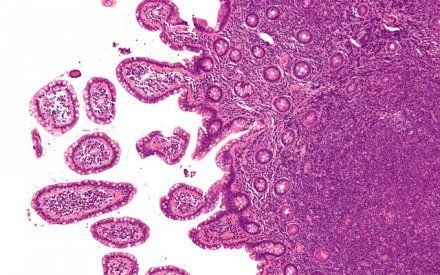

Phát hiện u lympho không Hodgkin tế bào B lớn lan tỏa

Tại Bệnh viện, bệnh nhân được bác sĩ thăm khám kỹ lưỡng và làm các xét nghiệm cần thiết. Kết quả xét nghiệm máu và tủy đồ cho thấy số lượng tế bào bất thường tăng cao, nghi ngờ bệnh lý ác tính về máu. Tiếp đó, kết quả chụp PET/CT phát hiện nhiều hạch trung thất và hạch mạc treo – dấu hiệu gợi ý tổn thương u lympho. Các bác sĩ tiến hành sinh thiết tổn thương, hội chẩn nhóm chuyên ngành ung thư hệ tạo máu và đưa ra chẩn đoán xác định: U lympho không Hodgkin tế bào B lớn lan tỏa (Diffuse Large B-Cell Lymphoma – DLBCL).

Theo các bác sĩ Khoa Huyết học Lâm sàng, u lympho không Hodgkin tế bào B lớn lan tỏa (DLBCL) là thể bệnh phổ biến nhất trong nhóm u lympho không Hodgkin. Bệnh xuất phát từ tế bào B – một thành phần của hệ miễn dịch, khi bị đột biến sẽ tăng sinh mất kiểm soát và hình thành các khối u ác tính.